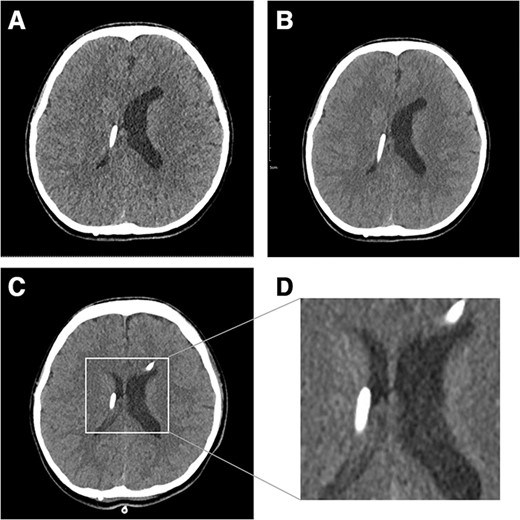

Fifteen years after shunt surgery, she began to visit ER with headache and vomiting. Her shunt pressure setting was upgraded in every visit but the pressure adjustment did not improve her symptoms, and the pressure was lowered from 2.5 to 1.5. Two months later, she returned to the ER with headache. Brain CT still showed slit-like ventricles with more collapsed right ventricle where the proximal catheter was located (Fig. 1A). Her headache did not improve with analgesics or mannitol administration. We tried to upgrade pressure levels to 2.0, but multiple attempts failed because she could not endure headache aggravation whenever the pressure level was upgraded. The CT scan taken after the pressure level upgrade to 2.0 showed no change in the collapsed right lateral ventricle (Fig. 1B). To overcome the resistance of stiff ventricular walls, an external ventricular drain (EVD) was inserted into the left lateral ventricle for temporary relief of ICP, with simultaneous upgrading of shunt pressure level to 2.5. The EVD opening pressure was high (22 mmHg). She had intermittent headache, but her symptom decreased gradually for 2 days after EVD insertion. On the 3rd day, follow-up brain CT showed a slightly expanded right lateral ventricle, and the patient stopped complaining of headache (Fig. 1C and D). The EVD was maintained for 2 more days and removed (Fig. 2). The patient was discharged while maintaining the shunt pressure level at 2.5. She is still doing well without headache after 15 months.

Fifteen years after VP shunt brain CT shows slit-like ventricle. In particular, the right ventricle collapsed where the proximal catheter was located (A). After a shunt pressure upgrade with mannitol administration, the patient’s symptoms worsened, and brain CT showed a collapsed ventricle (B). Three days after EVD insertion, the right ventricle was enlarged (C). Magnified image of enlarged ventricle (D).